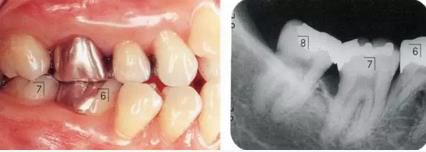

360截圖20170422101820545.jpg

▲圖5-3,4

▲圖5-3 開(kāi)始正畸治療時(shí)的側(cè)方照。預(yù)計(jì)使左下6向遠(yuǎn)中、左下5向頰側(cè)方向移動(dòng)。

▲圖5-4 在左下4~右下3的舌側(cè)種植支抗,并用金屬網(wǎng)增加強(qiáng)度。

360截圖20170422101831311.jpg

▲圖5-5,6

▲圖5-5 正畸治療結(jié)束后,佩戴臨時(shí)修復(fù)體以使牙列保持穩(wěn)定。

▲圖5-6 較深的牙周袋,正畸治療后留有骨組織高低差,左下6根分叉病變,附著齦不足等問(wèn)題,采取骨外科處理與FGG并用的手法進(jìn)行治療。左下6進(jìn)行牙根分割處理。